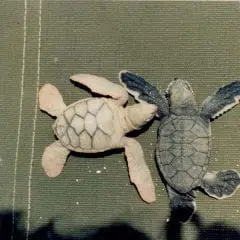

2012- Photo Depictions of Auto-Grafting a Juvenile Green Turtle.